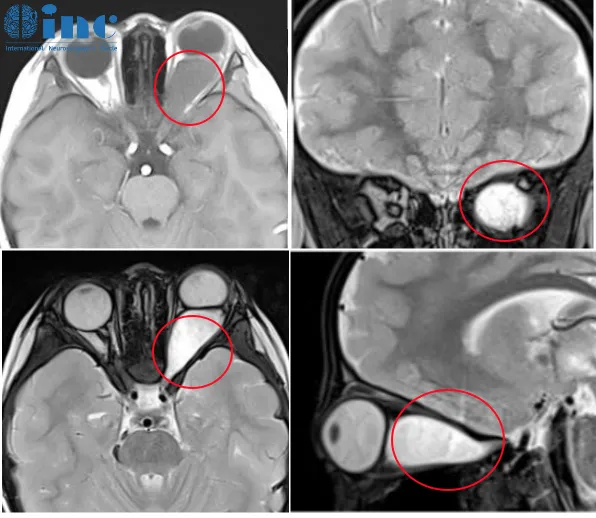

視神經(jīng)通路膠質(zhì)瘤(optic pathway glioma,OPG),也稱為視神經(jīng)膠質(zhì)瘤、視路膠質(zhì)瘤(本文統(tǒng)稱視路膠質(zhì)瘤),是發(fā)生在視神經(jīng)和/或視交叉的低級別星形細(xì)胞腫瘤,呈散發(fā)性或見于1型神經(jīng)纖維瘤...

視神經(jīng)-下丘腦低級別膠質(zhì)瘤能治好嗎? 視神經(jīng)-下丘腦膠質(zhì)瘤是典型的低級別星形細(xì)胞瘤,發(fā)生在視神經(jīng)通路的任何一點(diǎn),可能累及下丘腦。它們相對少見,通常出現(xiàn)于兒童,在20-30%的...